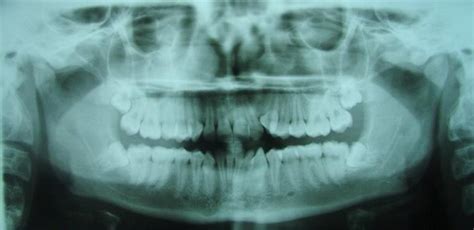

Figura 5 Telerradiografía lateral de cráneo pretratamiento.

La telerradiografía lateral de cráneo inicial (fig. 5) evidencia el resalte existente, con una mandíbula que presenta características típicas de tener un buen potencial de crecimiento.